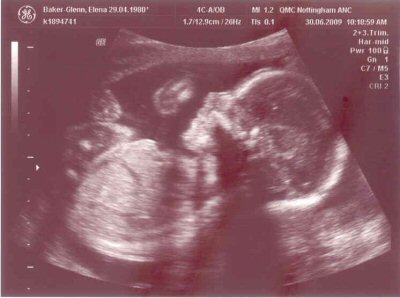

- The scan photos shown below were from the 20 week scan which was done on the 30th June 2009 when the gestational age was 21 + 2 weeks.